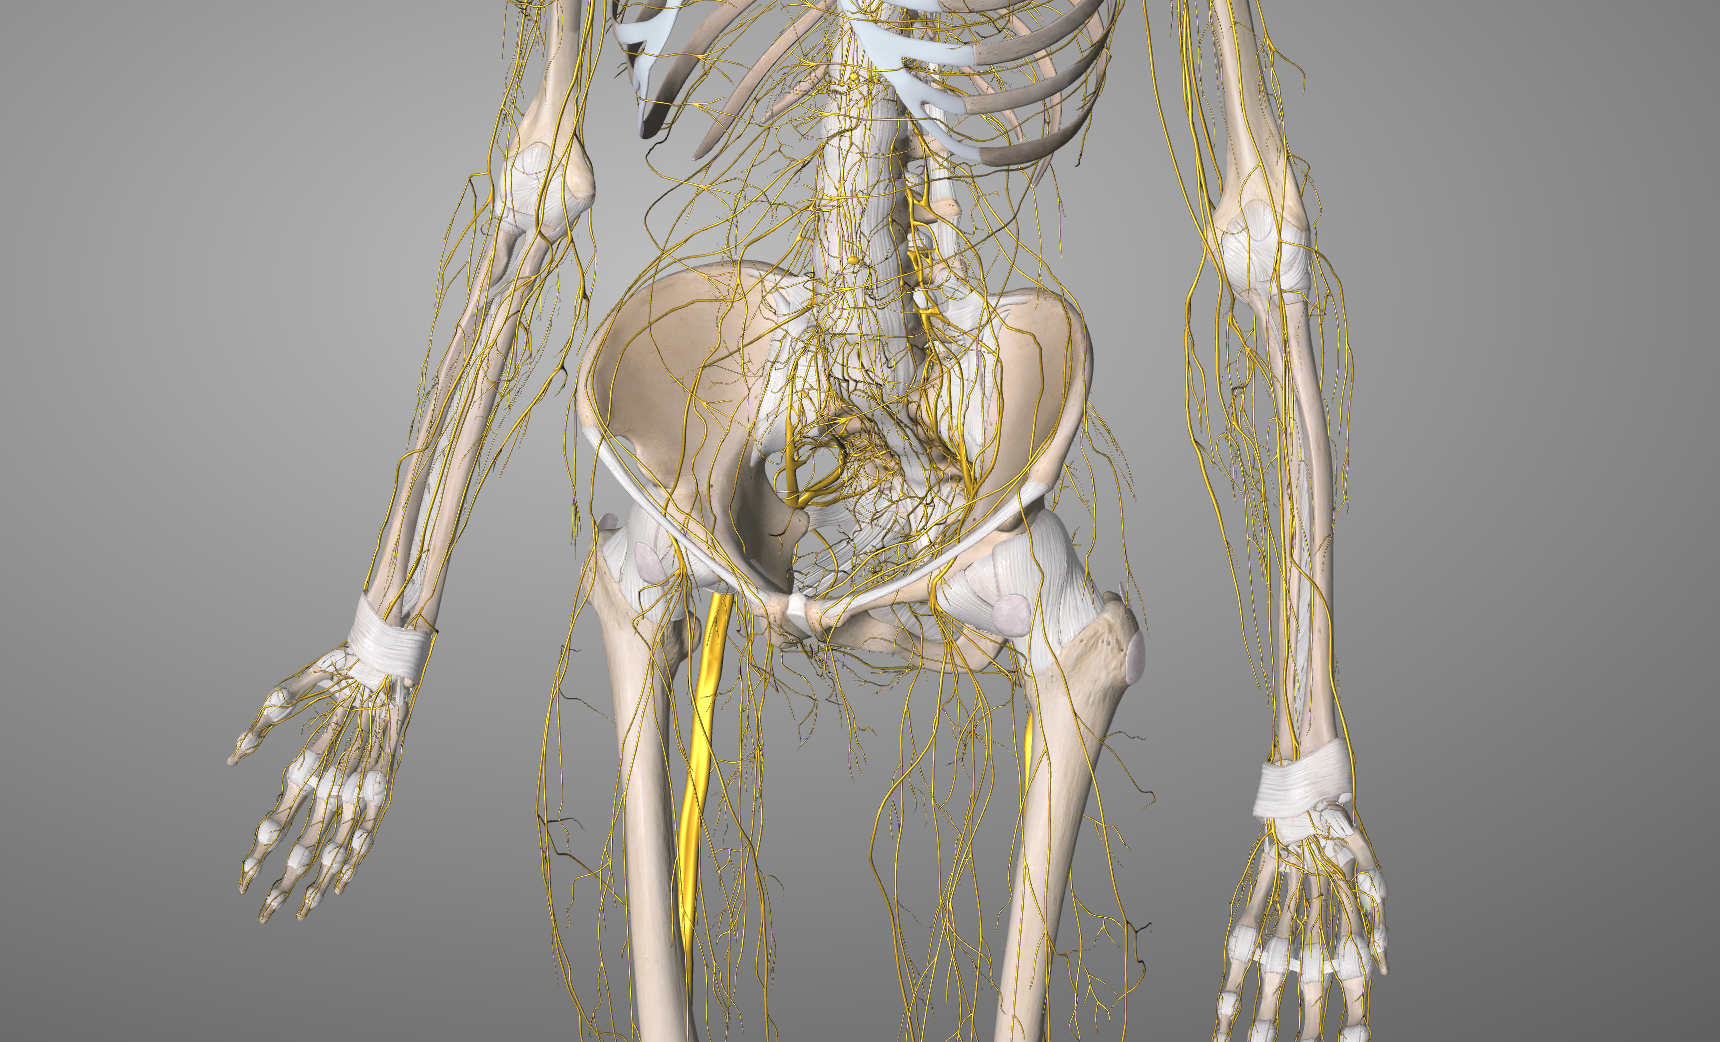

QUÉ ES LA NEURODINÁMICA: La técnica de neurodinámica se utiliza en fisioterapia para evaluar y tratar disfunciones del sistema nervioso periférico que afectan a su movilidad, sensibilidad y función . Su objetivo es mejorar el deslizamiento, la elasticidad y la capacidad de adaptación de los nervios dentro de sus interfases anatómicas. La NEURODINÁMICA como tratamiento, es una técnica que nos ayuda, por lo tanto, a movilizar o poner en tensión el sistema nervioso a través de lo que denominamos su interfase. El término i nterfase se refiere a las estructuras anatómicas que rodean, soportan y guían el recorrido de un nervio, influyendo en su movilidad y función. EJEMPLOS DE INTERFASES EN EL CUERPO HUMANO -Interfase ósea : Forámenes vertebrales por donde pasan las raíces nerviosas (por ejemplo, el agujero de conjunción para el nervio ciático en la columna lumbar). -Interfase muscular : El nervio mediano en su paso entre los músculos del antebrazo (pronador redondo), o el nervio ciático bajo el músculo piriforme. -Interfase fascial : Relación del plexo braquial con la fascia del escaleno en la salida torácica. -Interfase vascular : Relación del nervio con arterias y venas que pueden influir en su función por cambios hemodinámicos o compresiones. Cuando hay disfunción en una interfase , la mecánica del nervio se ve afectada, pudiendo generar atrapamientos o restricciones al deslizamiento neural. Aquí es donde los test neurodinámicos y las técnicas de movilización neural juegan un papel clave en la evaluación y tratamiento. TIPOS DE MOVILIZACIONES DE NEURODINÀMICA -MOVILIZACIÓN PASIVA y PASIVA-ASISTIDA: Aplicada por el fisioterapeuta para movilizar el nervio sin esfuerzo del paciente. MOVILIZACIÓN o DESLIZAMIENTO: -Desde un extremo -Desde los dos extremos (como en el ejemplo de las fotos en el que la paciente ladea la cabeza hacia el lado contrario al que estamos tratando al tiempo que flexionamos el codo y al revés ocurre en el recorrido contrario, extendemos el codo mientras la paciénte lleva la cabeza a su posición neutra). PUESTA EN TENSIÓN -MOVILIZACIÓN ACTIVA: El paciente realiza movimientos coordinados para mejorar la movilidad del nervio dentro de su interfase EJERCICIOS ACTIVOS (flossing o deslizamientos): El paciente realiza movimientos coordinados para mejorar la movilidad del nervio dentro de su interfase. Los grados de puesta en tensión se deberán adaptar a la sintomatología del paciénte, respetando las barreras que vayan apareciendo y que limitan la movilización.